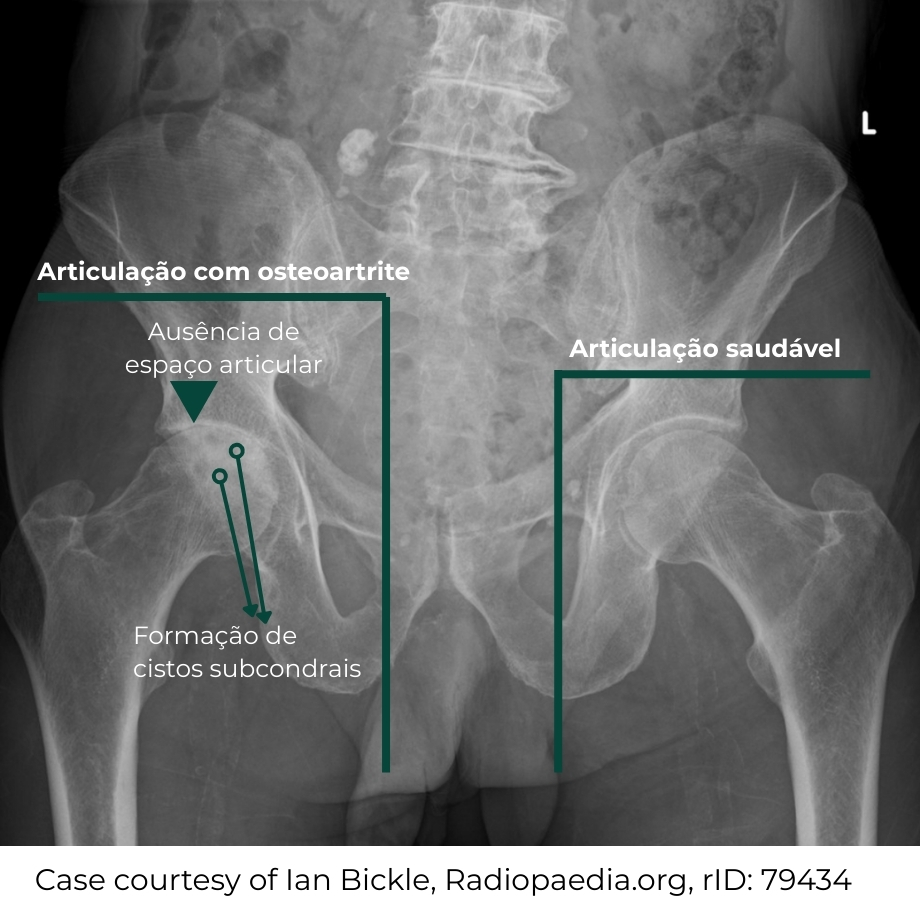

Radiografia do quadril com achados típicos de osteoartrite: Ao lado direito observa-se redução do espaço articular, esclerose óssea, formação de osteófitos e alterações no contorno da cabeça do fêmur e do acetábulo, compatíveis com desgaste da articulação.

A radiografia permite avaliar de forma clara:

• redução do espaço articular;

• presença de osteófitos;

• esclerose óssea;

• alterações no formato da cabeça do fêmur e do acetábulo